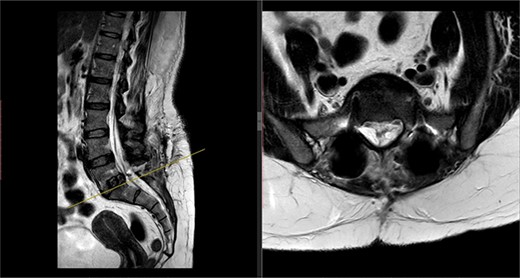

Postoperatively, the patient developed severe radiculopathy down the left leg and required opiates. The patient could not move the left leg and was unable to mobilize. X-rays showed the implants were in position (Fig. 3), but the information from a fresh MRI scan was limited due to metal artefact (Fig. 4). With ongoing, unrelenting pain, she was returned to theatre on the fourth postoperative date, and the wound was re-explored. Intraoperatively, no dural tear was identified, the nerve roots were free, and the screws appeared in position. She was then discharged home after ten nights in hospital, instead of the standard three nights that would be common practice.

Postoperative X-ray of the lumbar spine performed in January 2017, showing the implants in place.